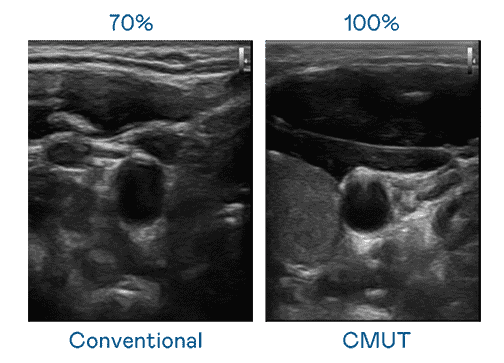

CMUT 技术是一种用电容式微机电元件来产生超音波讯号的技术。。与传统 PZT 压电式技术相比,,,CMUT 频宽增加 30%,,,,更宽频的超音波讯号让影像解析度大幅提升,,,是实现高影像品质医疗超音波扫描、、、、促进精准医疗发展的关键技术。。。

超音波影像的解析度高低,,首先取决于探头能发出的讯号频宽。。2121非凡 CMUT 可提供高清晰的超音波讯号,,,,提供高频宽、、、高灵敏度、、、、影像纹理细节更高的超音波影像,,,协助医护人员缩短影像判读时间及利用精准的医疗影像进行诊断。。